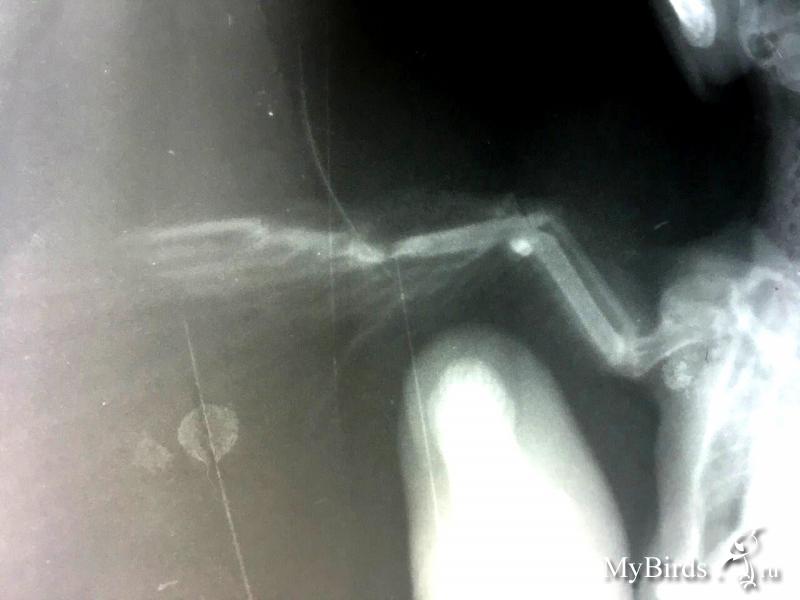

foto2015 Опубликовано 2 мая, 2017 #1 Опубликовано 2 мая, 2017 Добрый день! Подобрали стрижа с переломом. Подскажите в отношении лечения что можно сделать.Спасибо.

Anysya Опубликовано 2 мая, 2017 #2 Опубликовано 2 мая, 2017 значительного смещения нет, шанс есть. но не 100%. при таком переломе рентген в полной раскладке опасен( можно доломать, были случаи. фото птицы в позиции сверху и сбоку со стороны больного крыла. как складывает крылья, висит ли поврежденная часть крыла? что можно сделать - 2 недели СТРОЖАЙШЕГО карантина. большая картонная коробка, бумажные, постоянно меняющиеся салфетки на дно. можно полотенце-присаду на стенку. сверху обязательно должна быть вентилируемая крышка, на которую не сможет залезть, из под которой не сможет выбраться.ТЕМНОТА. тишина, покой. еда - кормовые насекомые в достаточном количестве. кормить, при условии что птица не ест сама только завернув в одноразовое полотенце и тп. аккуратно. целостность и чистота пера - такой же залог возможности полета. поить очень умеренно, но хотя бы раз в сутки воду предлагать. исходить из возможности того, что у птицы еще и чмт. для стрижа это почти 100% вероятность.траумель ампульный по 0,05 мл в сутки 2 недели. спаивать.б1 ампульный 0,04 мл + столько же таурина (глазные капли тауфон) - споить сейчас однократно и потом раз в неделю. всего на земле птица должна провести НЕ МЕНЬШЕ полутора месяцев. СТРОГО. попытка выпустить раньше - выкинуть птицу, даже если она взлетит. 2 недели карантина - на сращивание кости. не обезбаливать НИЧЕМ. боль - единственное. что заставляет птицу беречь крыло, держать его в покое. можете, проходя мимо, класть больное крыло поверх здорового на спине, приучая птицу сидеть именно в этой позе. повязок НЕ НАДО.месяц после этого нужен для образования достаточной костной мозоли. без этого при полетных нагрузках стрижа птица снова упадет. только ей уже не повезет попасть к вам. при любых изменениях в состоянии, угрозе жизни, судорогах и тп - пишите сразу.есть вопросы - задавайте. по выпуску - пишите как пойдет выздоровление. там посмотрим.

Anysya Опубликовано 2 мая, 2017 #4 Опубликовано 2 мая, 2017 понятно... тогда половину написанного выше можно забыть. просто перед рентгеном крыло удачно сложили. собственно, стрижу с открытым переломом рентген делать особо незачем. разве что убедиться, что нет других повреждений. птица не полетит. стрижи не летают после переломов со смещением. это пмж.кроме того, вам необходим антибиотик широкого спектра и покрытие - гепапротектор и противогрибковое.подойдут (на выбор) амоксициллин (синулокс вет., либо амоксиклав чел. 120 мг/кг в сутки. разбить на 2 приема обязательно. удобно давать в насекомом, не в клюв. чтобы не вдохнул. туда же по 2 шарика ирунина и микродозе карсила), либо энрофлоксацин, либо ципрофлоксацин. пишите. что у вас есть, чтобы уточнить дозировки по другим препаратам.саму рану, если необходимо, обрабатываем хлоргексидином. ничего спиртосодержащего, никакого лидокаина. для реабилитации режим и сроки те же. но крыло необходимо сложить. нужна повязка. к телу НЕ приматывать. такая корзина приемлема для поездок, в некоторых случаях - в доме кошки и тп - для содержания. для реабилитации не подходит. птица может доломать себе что-нибудь. сожалею.